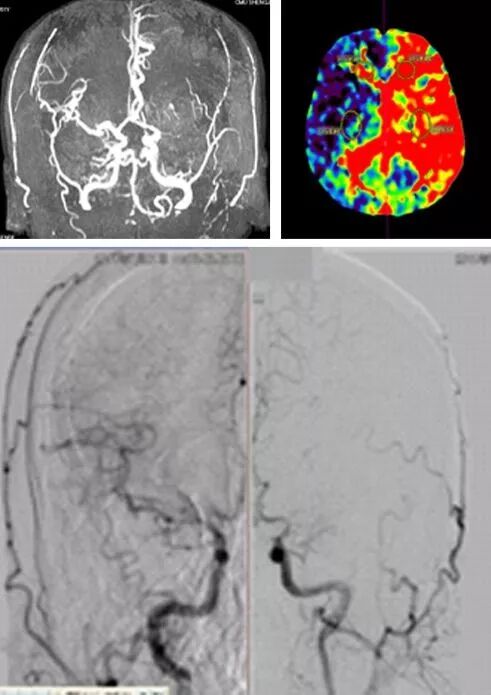

男患,61岁,既往TIA病史,突发右侧肢体活动不灵3个月,经头MRA、CT灌注成像、DSA检查并排除其他疾病后,诊断该患为烟雾病。临床分期及分型:Suzuki及Takaku III期,Matsushima III型。

患者术后1个个月和3个月分别复查CTA及DSA见血管吻合确切,血流通畅。

术前(左侧)与术后(右侧)左侧大脑半球供血血流的对比,术后患侧大脑半球血运很大程度增多。